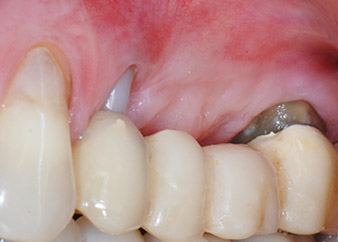

A 58-year-old female patient complained of pain and increased mobility of her bridge abutment tooth 24. Periodontal inflammation was present with pocket depths of 7 mm mesiobuccally and more than 12 mm distally, as well as third-degree furcation involvement. Moreover, the radiograph revealed an extensive periodontal lesion around the apical region of the (alio loco) endodontically pretreated tooth 24 (Fig. 1).

One year earlier, teeth 25 and 26 had been extracted due to trauma and for endo-perio reasons, prior to the placement of the bridge. A combined endo-perio lesion was diagnosed for tooth 24, of unclear aetiology. The patient wanted to keep her bridge abutment teeth 24 and 27 and would not accept a final, or even temporary, removable prosthesis. Therefore, it was agreed to make all efforts to retain both teeth, in spite of their poor prognosis as based on radiological and clinical findings.

One month later, on the day of surgery, pain and inflammation at tooth 24 were minimal, but mobility of Miller class 2 was still present. After opening the flaps and cleaning the periapical and peri radicular infected tissue, the extent of the bone defect became obvious (Figs. 2 and 3).

At the buccal root, all vestibular and distal bone was missing. Attachment was essentially restricted to the palatal root, underlining the preliminary poor prognosis. Tooth 27 also showed a reduced horizontal attachment and a minimal apical rarefaction (cf. Fig. 1) without clinical symptoms.